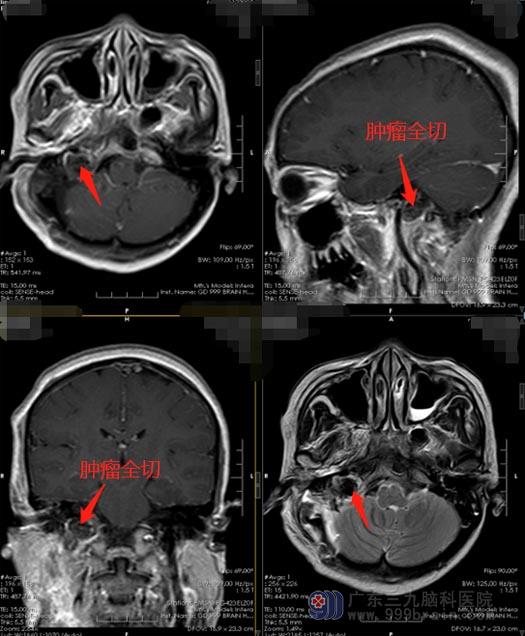

入住广东三九脑科医院后,医院副院长、神经外五科主任鲁明带领团队对林大姐的病情进行了仔细的讨论,完善相关检查后,由鲁明主刀在全麻下行“右侧颈静脉孔区颅内外沟通神经鞘瘤切除术”,显微镜下全切直径约3cm的肿瘤,术中面、听、三叉神经保留完好。术后林大姐无咳嗽,吞咽困难症状得到改善,已顺利康复出院。